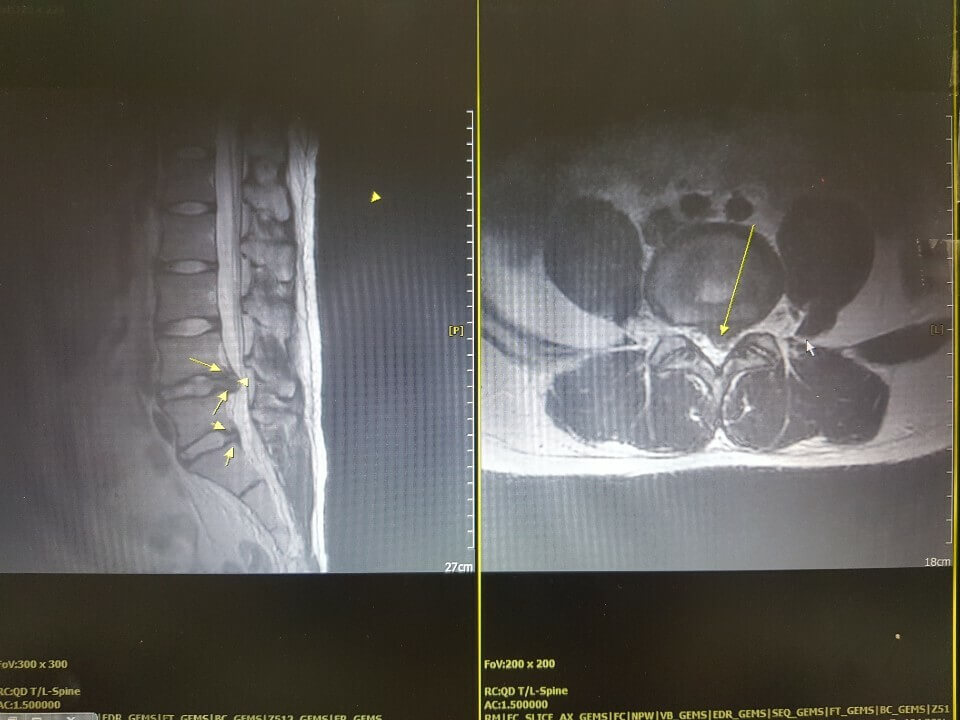

추간판 탈출증이라 불리는 허리디스크 증상은 크게 3단계로 나눌 수 있어요. 1단계는 내부 섬유륜이 파열하여 수핵이 빵빵한 상태, 2단계는 섬유륜 전체가 파열되어 수핵이 탈출하는 단계, 3단계는 완전히 탈출해 버린 단계입니다.

단계마다 느끼는 증상들이 조금씩 다른데요. 디스크의 보호막이 약간 찢어졌고 디스크가 약간 튀어 주변의 신경 뿌리에 닿으면 염증성의 통증이 발생하기 시작하면서 점점 증상이 심해지면 디스크의 파열은 골수를 이루고 있는 핵이 튀어나오면서 신경에 대한 물리적 압박을 가하고 참을 수 없는 아픔을 유발하게 돼요.

디스크의 초기 증상을 살펴보면 추간판 디스크 파열에 비하여 눌리게 된 디스크 양이 많지 않으니, 신경에 대한 물리적 압박이 그다지 심하지 않다고 볼수는 있어요. 하지만 마비 증상과 근력 저하의 증상으때문에 한쪽 다리나 또는 양쪽 다리에 저림이 발생할 수 있어요. 또한 허리주변이 아프거나 허리의 통증을 느끼는게 있다고 합니다. 혹시라도 이러한 증세를 겪고 있다면 디스크의 초기 증상은 아닌지 확인할 필요가 있다고 합니다.